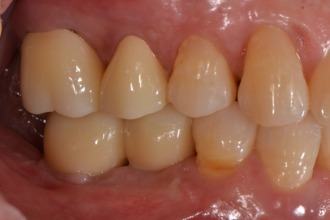

심미보철치료